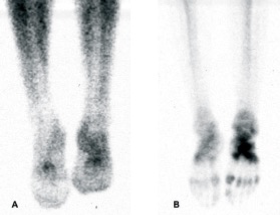

Centollografía ósea:

Metilen-difosfonato.

Leucocitos marcados con indio-111 o tecnecio-99m.

Falsos positivos: pie de Charcot, gota, trauma, cirugía.

Centellogafía ósea:

Modo de tres fases:

* Primera fase: imágenes dinámicas, 1 min posterior a la infusión del radio trasador.

* Segunda fase: estado estable, imágenes estáticas, se toma la región de mayor interés, 5 minutos después de la infusión.

* Tercera fase: imagen de cuerpo entero, 2 hrs después de la infusión